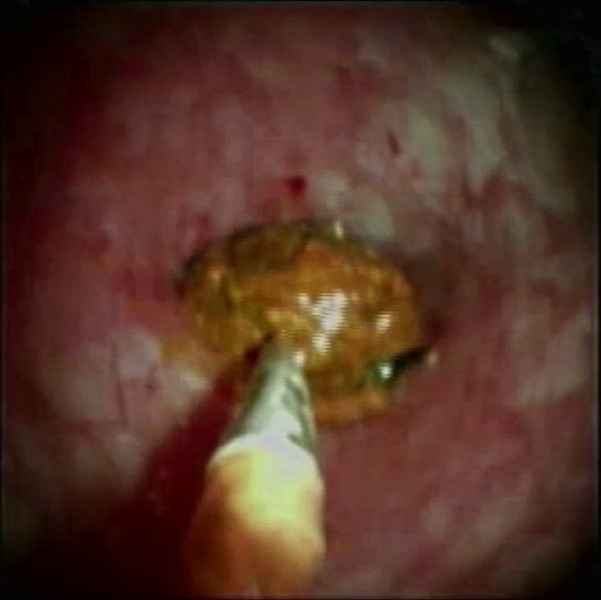

A mantle of rosaries along the colon - 2.º Prémio (Fotografia)